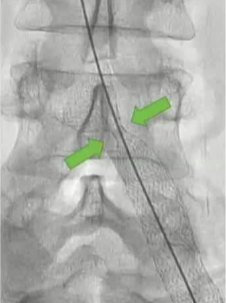

该病变先使用了一个直径为 14 毫米、压力为 20 大气压的球囊进行了 20 秒的预处理!

其它考虑怎么做?How to do IT? 1. 建议将静脉段的扩张程度控制在与所选支架直径相匹配的范围内。【Rahmani 2023 Gibson 2022 Cirse SOP 2014 Raju 2013】 狭窄血管的过度扩张通常不会导致破裂,即便在慢性闭塞的情况下,血管也能承受较大的球囊扩张,并在随后置入较大的支架而不会发生破裂。 只有在以下情况才需例外处理:即在腹膜后区域或鞘管 环绕外科手术已经打开的静脉【joyce DP 2024】 对于慢性静脉阻塞的情况,采用逐渐增大直径的球囊进行多次扩张操作可能并非必要。 除非您无法将 14/16 毫米的气囊顺利穿过病变部位,否则可能需要进行多次扩张操作。【Barbati 2014】 2. 此外,该操作应贯穿整个病变部位的整个长度进行。【Oropailo 2023 Lichtenberg 2018】 ![]() 3. 使用高压球囊【Oropallo A 2023 Gibson 2022】 44岁 男 2次左髂股静脉血栓形成,以下静脉造影